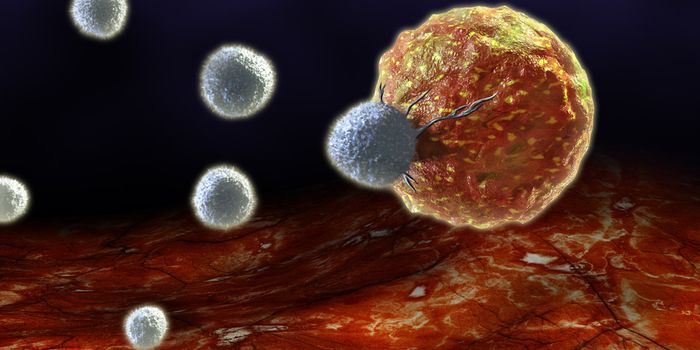

NOV 20, 2019ImmunologyManipulating the immune system’s population of natural killer cells could bolster therapies targeting cancer. A ne ...

SEP 17, 2015ImmunologyCancer immunotherapy efforts have been mainly concentrated on the adaptive immune system, some even connecting epigeneti ...

MAY 16, 2024CancerThe immune system provides an integral defense against cancer growth and progression. Activating an anti-tumor immune re ...

DEC 10, 2015ImmunologySuperior technology brings us novel images of cancer cells and lymphocytes this week, and now scientists can learn more ...

NOV 30, 2023CancerCytotoxic T cells (CTLs), a type of immune cells integral to fighting cancer, rely heavily on interaction with a molecul ...

JAN 25, 2024CancerImmunotherapies have drastically altered the scope of cancer therapies in the past decade. Immune-based approaches ...